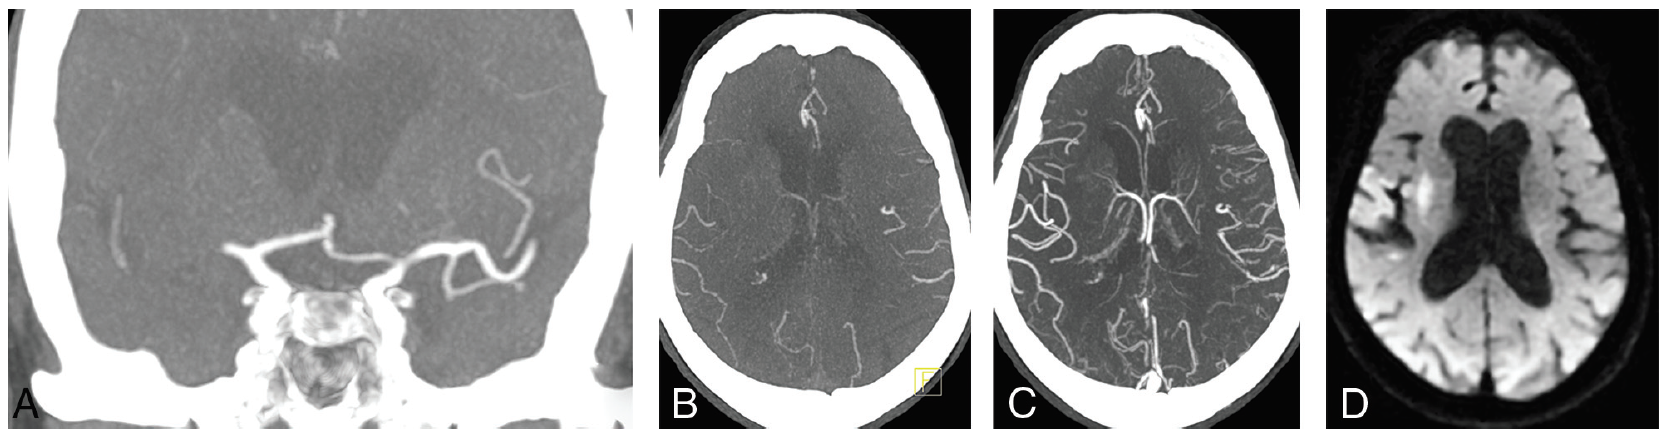

侧支循环评估: